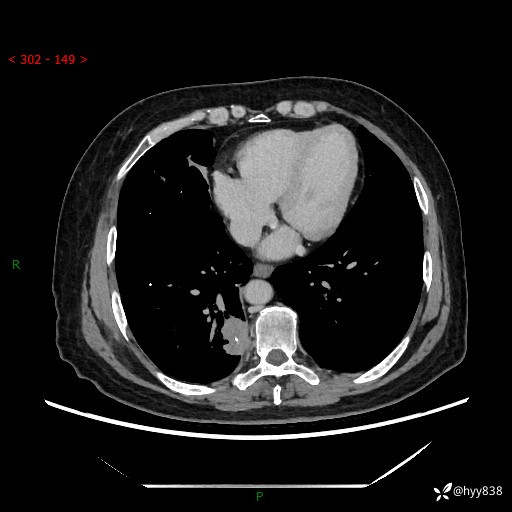

增强动脉期+静脉期

两期CT值:55Hu 53hu